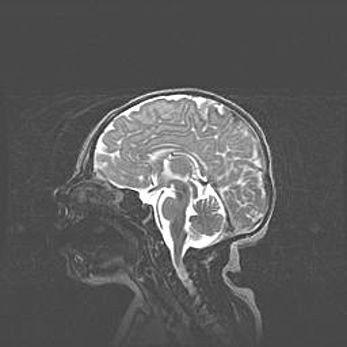

Неполная лизэнцефалия (пахигирия). Открытая гидроцефалия.

Возраст: 17 дней

Вес: 3110 г

Пол: мужской

Окружность головы: 33,5 см

Срок гестации: 35-36 недель

Лизэнцефалия—недоразвитие корковой пластинки и мозговых извилин в результате нарушения миграции нейронов коры. Поверхность мозговых полушарий гладкая. Микроскопически выявляется отсутствие нормальных слоев коры и скопление групп нейронов в подкорковом белом веществе.

Пахигирия—уменьшение числа вторичных извилин. В пораженном полушарии нервные клетки образуют толстый недифференцированный слой с неправильно расположенными нервными волокнами и группами гетеротопных клеток. Нервные клетки незрелые. Белое вещество истончено. При этом нередко аномально развит корково-спинномозговой путь.